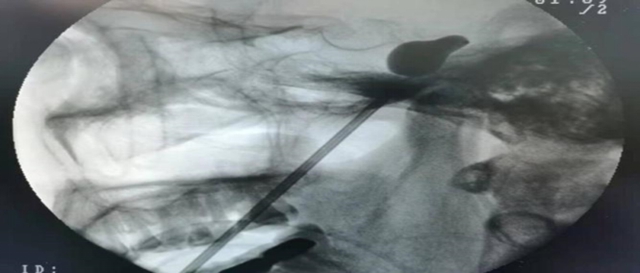

术中,团队在C型臂引导下,精准将微球囊置入颅底卵圆孔完成压迫后取出,全程耗时短、创伤小,充分体现了该微创术式的临床应用优势。

经皮穿刺三叉神经微创球囊压迫术(PMC):患者在全麻下,经C形臂的引导,从面部皮肤穿刺达到三叉神经出颅腔的部位——卵圆孔,以球囊导管置入麦克氏囊,通过球囊扩张适度压迫三叉神经半月节,充分阻断三叉神经的痛觉神经元,达到治疗的目的。